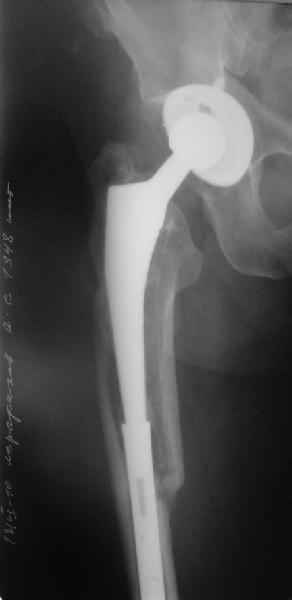

Уважаемые коллеги, в данном случае в лечении стандартного перипротезного перелома В2 Ванкуверской классификации (перелом вокруг ножки эндопртеза с потерей стабильности ножки при хорошем - не требующем пластики - качестве кости.Parvizi J, Rapuri VR, Purtill JJ, et al (2004) Treatment protocol for proximal femoral periprosthetic fractures. J Bone Joint Surg Am; 86-A Suppl 2:8-16)с успехом применён оригинальный, но малоизведанный способ лечения подобных повреждений. В результате и последующие рекомендации не могут быть стандартными. В подобных случаях, как это уже дискутировалось год назад, можно было выполнить ревизию длинной ножкой, во многом работающей как интрамедуллярный гводь + плюс кабель/серкляж в проксимальном отделе. Или, оставить имеющуюся ногу плюс длинная пластиа с кабелем/серкляжем, можно разными современными блокированными *примочками*. В таком случае при достижении консолидации пластина удаляется, тк при возникновении в будущем потребности в ревизии имеющийся дополнительный металл и без затруднит непростое вмешательство (кто пробовал, знает о чём я говорю). С длинной ногой, конечно, так же всё понятно. В данном случае мы имеем некую комбинацию, осложнённую отсутствием репозиции и фиксации в прошлом отломков вокруг ножки. Поэтому не каждый в данном случае рискнёт утверждать за счёт какого из компонентов системы - дистального либо проксимального обеспечивается стабильность. А если это и фиксация и за счёт ножки и за счёт гвоздя - каков баланс между данными компонентами в поддержании стабильности ситемы. То есть, я надеюсь, что дистального смещения ножки здесь не будет при условии сохранения как гвоздя, так и блокирующих винтов. При удалении же гвоздя возможна миграция ножки, только винтов - всей системы. Здесь же перелом (надеюсь, его не будет) блокирующих винтов может быть первым свидетельством механического неблагополучия системы... А так, помимо отличного результата этот случай так же косвенно подтверждает известную истину - Эндопротез, к сожалению, требует периодической замены. И выполняя фиксацию перипротезного перелома, а в последующем решая вопрос об удалении имплантатов, мы вынуждены думать и о функции сустава, и о том, как в будущем выполнить ревизию. Если ожидаемая продолжительность жизни пациента заставляет нас об этом думать. С уважением, Андрей

Уважаемый Александр Николаевич,

Как Вы знаете, мы имеем негативный опыт подобной операции (перелом ножки эндопротеза на месте соединения со штифтом), но тем не менее хотелось бы сказать следующее. На мой взгляд,выполняя такую фиксацию, мы становимся заложниками сохранения всей этой мегаконструкции на долгое время, если не на всю жизнь. Эта система работает уже как единое целое. Рефиксации ножки эндопротеза не произошло, при удалении гвоздя может развиться вторичная нестабильность, скорее всего со временем произойдут дистрофические изменения в кости за счет шунтирования нагрузки. Поэтому есть смысл отследить очень тщательно р-ты этих операций, прежде чем они войдут в повседневную практику, думаю что показания к ним будут весьма ограничены. Пару раз попробовали "пошалить", собрали бедро на бесцементной ножке у пожилых б-х дабы не утяжелять вмешательство. В одном случае - срослось и ножка получила стабильность, в другом - потребовалось реэндопротезирование, но со значительно меньшей травмой. т.к.бедро срослось.